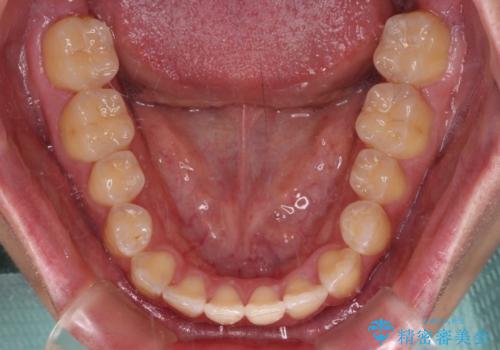

当初予定通り、1年間で治療を終えることができました。

ワイヤー矯正でもマウスピース矯正でも可能でしたが、短期間で、自身の手を煩わせることなく治療を行いたいとのことで、ワイヤー装置にて矯正治療を行うこととしました。